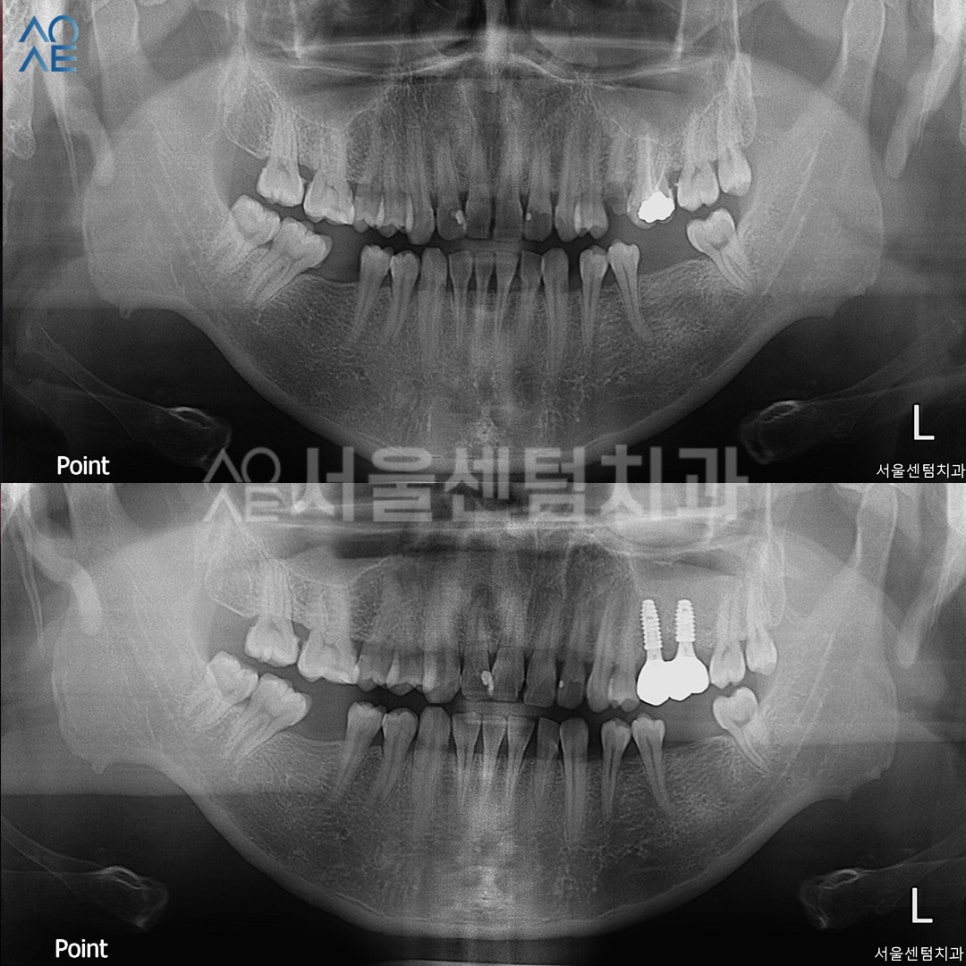

| 🦷현재 상태 &치료 계획🦷 |

|---|

| (1) 현재 상태🔹 왼쪽 작은 어금니 깨진 상태, 그 옆 어금니도 상태 좋지 않음🔹 오른쪽, 왼쪽 아래 어금니 상실 |

| (2) 치료 계획🔹위쪽은 상악동수술 동반한 임플란트 진행🔹아래쪽은 더 고민하고 진행해보시기로 |

| ✅왼쪽 위 어금니 발치✅CT촬영하여 정확한 상악동 위치 파악✅수직 상악동수술 + 뼈이식 + 임플란트 식립✅보철물 수복 |

아래쪽 어금니는 이미 상실한 상태여서

임플란트 치료가 필요했지만

환자분께서 윗쪽 먼저 진행하고 싶다고 하셔서

윗니 발치 후 임플란트 식립 계획을 세웠습니다.

특히 식립 및 상악동수술 하기 전에 CT를 촬영하여

정확한 상악동의 위치와

식립 위치를 확인하였습니다.